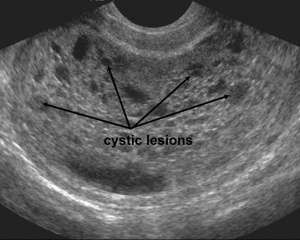

- Molar pregnancy

- Many small, irregular cystic structures in endometrium

- "Snowstorm appearance"

Pseudogestational sac Molar pregnancy with multiple cystic lesions in endometrium ("snowstorm appearance")

Molar pregnancy with multiple cystic lesions in endometrium ("snowstorm appearance")